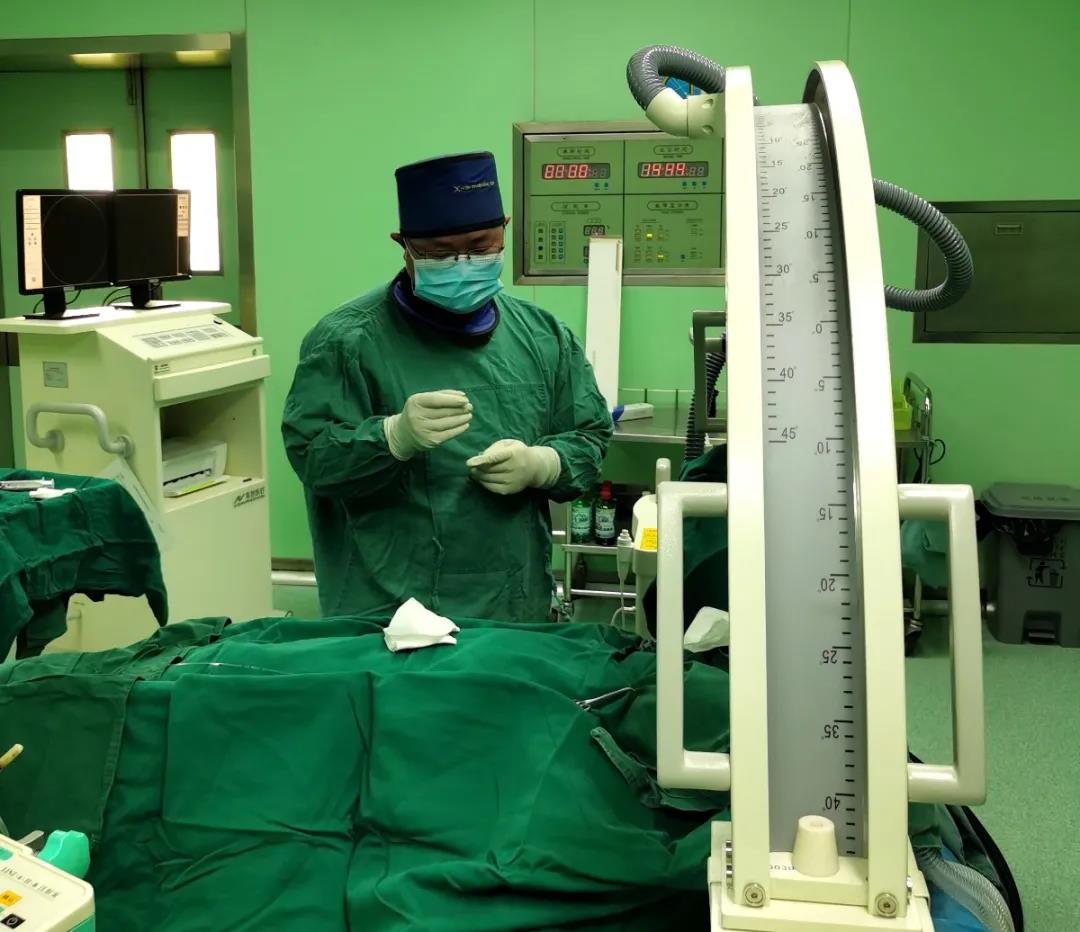

1月21日下午,我院心血管内科聯合新鄉醫學(xué)院第一附屬醫院神經(jīng)外科一病區成(chéng)功完成(chéng)一例三叉神經(jīng)半月節球囊壓迫手術,特邀一附院關慶凱副主任醫師前來主刀,在介入手術室等科室的配合下成(chéng)功爲患者解除了多年病痛,同時(shí)填補了我院在三叉神經(jīng)痛新技術領域的運用空白。

上圖爲關慶凱副主任醫師與我院心血管内科醫護人員共同攜手打造新鄉醫學(xué)院第一附屬新華醫院三叉神經(jīng)痛微球囊壓迫術,新鄉醫學(xué)院第一附屬醫院神經(jīng)外科具有二十多年的三叉神經(jīng)診療經(jīng)驗,精通各種(zhǒng)治療方式,已取得經(jīng)治患者廣泛的認可和好(hǎo)評,歡迎廣大三叉神經(jīng)痛患者咨詢。